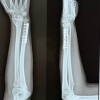

While A. Sarmiento was delivering his lecture on “Physiology of fracture healing”, his senior resident was sitting at the back of the hall and reading a newspaper. Needless to say any professor of the stature of Sarmiento, was annoyed and felt disrespected. He therefore asked him, for an explanation for his behaviour. The resident remarked that he was not interested in conservative managements and wanted to be taught how to fix the fracture surgically. In another lecture on “Role of hematoma, in fracture healing”, he stressed how by open reduction, you convert a closed fracture in open surgery and lose the hematoma and its effects on callus formation. He felt that most of his patients treated with a cast, would have nearly full range of movement, perhaps with a little deformity and shortening but in turn this would not come in the way of the functional demands of the patient.

A recent webinar on conservative treatment, discussed the Sarmiento technique in detail, in treating not only the humerus fracture, but also tibia, femur, and both bones forearm. The speaker effectively convinced the faculty and I am sure most of the viewers who had logged in, of the good results of simple and difficult fractures. Most importantly he mentioned about the absence of a scar, functional movements being full, and the patient is invariably happy that there is no surgery. He impressed upon how young female patients are willing and asking for conservative treatment to avoid a scar. He did mention about the importance of detailed counselling so that the patient makes a wilfully knowledgeable decision. In case of failure of conservative treatment, not getting the necessary results, one can always opt for surgical treatment. But will the doctor be taken to consumer court for want of proper care, resulting in cosmetic deformity and limitation of function?